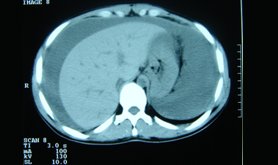

The CT scan of the abdomen is a very important medium by which one can manage abdominal disorders. The high resolution powers of the scanners make it possible to demonstrate the anatomy of the abdominal region and its associated ailments.

The CT Abdomen plain is used to figure out the defects in the abdomen by diagnosing the cause of the abdominal pain and disease of the internal organs, small intestine and colon which can be caused by any of the following: